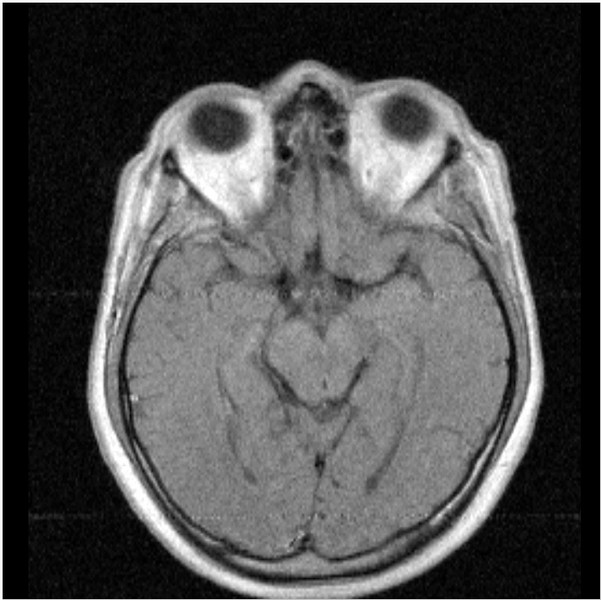

При обследовании головного мозга излучению подвергается только пораженная область, в то время как область малого таза остается вне воздействия. Тем не менее, эндокринная железа, отвечающая за регулярность цикла, расположена в нижней части мозга, и нарушения при проведении МРТ мозга не были зафиксированы. Процедуру можно проводить даже во время менструации, это не повлияет на состояние организма.